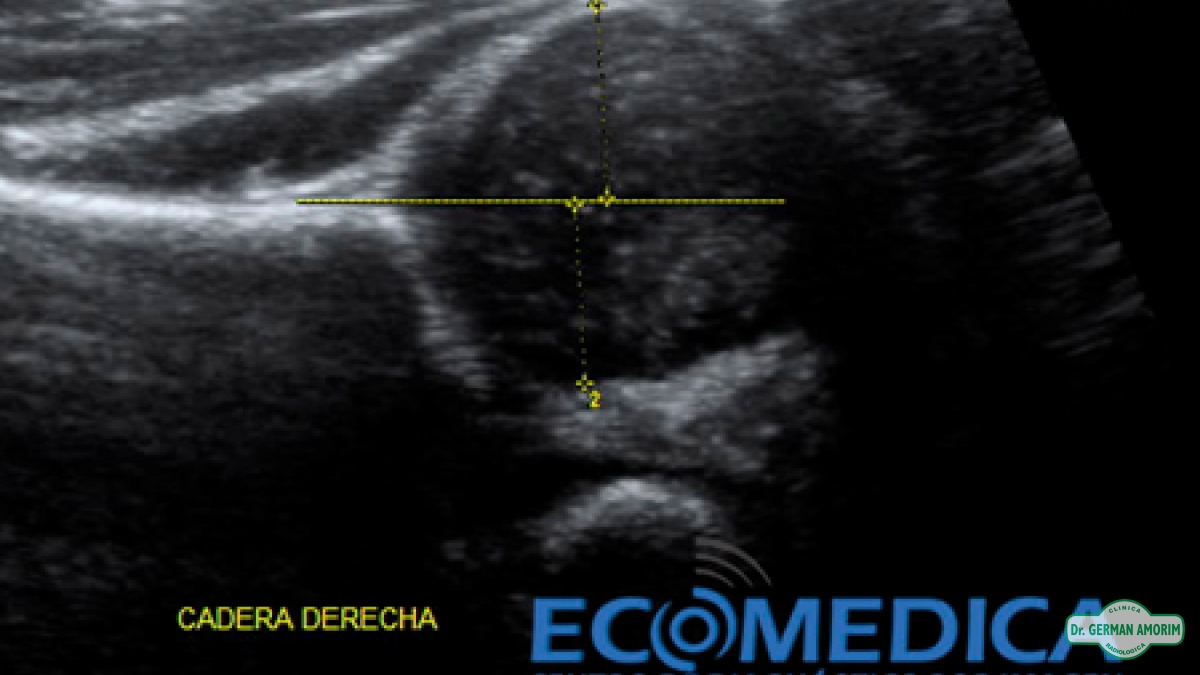

La ecografía de cadera es una prueba segura e indolora, en la que se utilizan ondas sonoras para generar imágenes de la cadera. Durante la exploración, el ecógrafo envía ondas sonoras al área de la cadera del bebé y las imágenes se registran en una computadora. Las imágenes en blanco y negro muestran las estructuras internas de la cadera, incluyendo la parte superior del hueso del muslo, en forma de bola (o cabeza del fémur) y el hueso de la pelvis.

En una cadera que funciona con normalidad, la cabeza del fémur descansa cómodamente en su acetábulo, o cavidad cotiloidea del hueso coxal. En los bebés con displasia evolutiva de cadera, la cabeza del fémur se mueve hacia adelante y hacia atrás dentro de esa cavidad. En los casos más graves, la cabeza del fémur se puede salir del acetábulo.